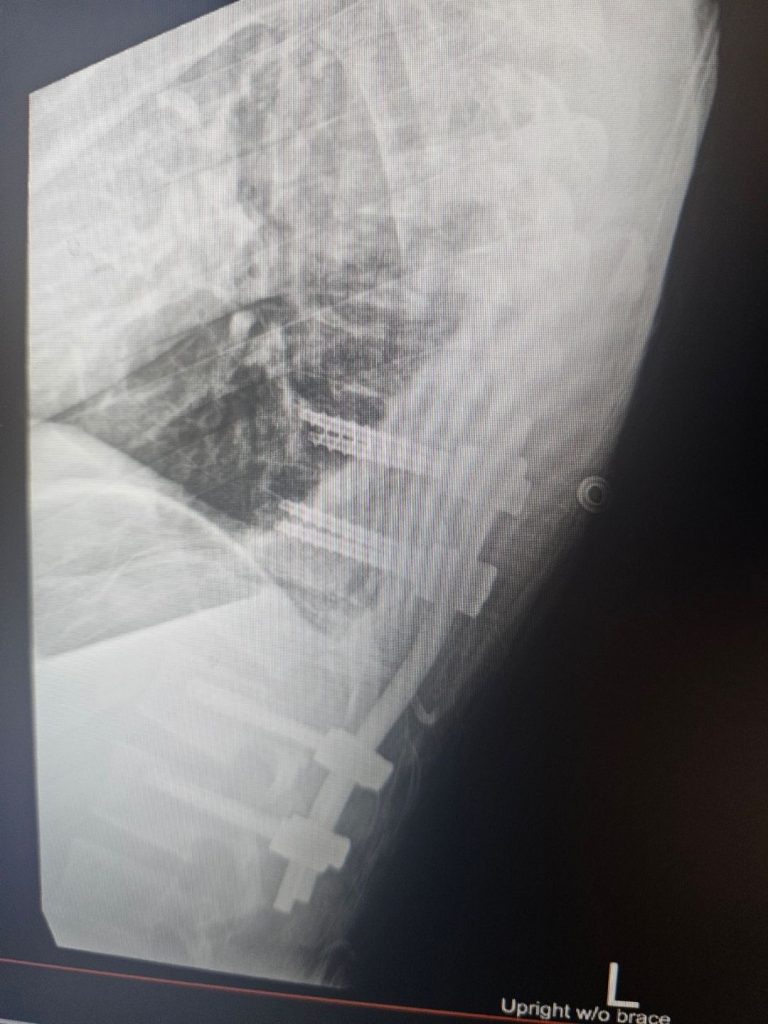

Roberts was then airlifted to a Boise hospital around 48 miles away where he underwent emergency surgery to stabilize his spine by addressing two spinal fractures. Besides the spinal fractures, he also suffered a broken clavicle and multiple rib fractures.